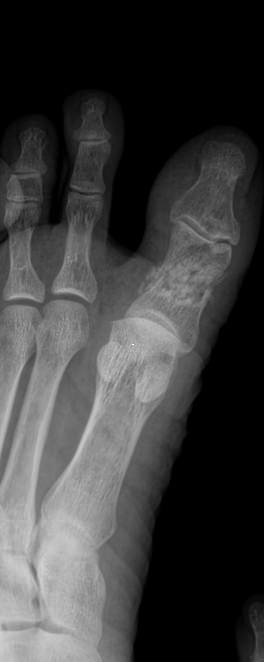

Все изменения хорошо видны на рентгеновском снимке, он и будет первым, а чаще и основным, видом диагностики. Основываясь на рентгенограмме, а также лабораторных показателях, врач выбирает оптимальное лечение и дальнейшее ведение болезни.

На прицельном снимке будут отчетливо видны следующие изменения:

• Суставная щель может быть расширена, в том числе неравномерно, или сужена, в ней обнаруживается выпот или участки обызвествления;

• Суставные поверхности могут не соответствовать друг другу из-за вывиха;

• В тканях кости и надкостницы обнаруживаются участки разрежения, уплотнения, разрастания, воспаления, перелома;

• Утолщение мягких тканей;

• Новообразования, при наличии.